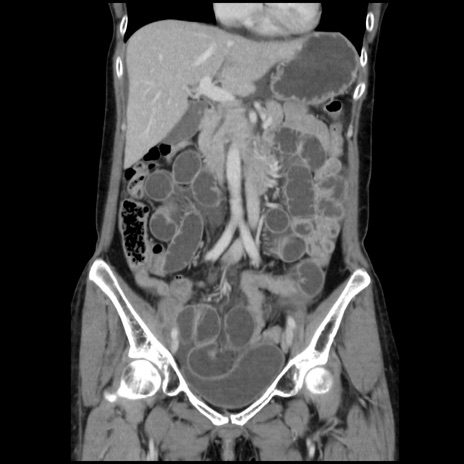

症例32(冠状断像)

【症例】40歳代 女性

【主訴】上腹部痛、嘔気・嘔吐

【現病歴】約9時間前頃から急に上腹部痛、嘔気、嘔吐が出現。改善しないため救急要請。

【既往歴】子宮頚癌(広汎子宮全摘術、放射線療法)、腸閉塞

【身体所見】腹部:平坦、軟、腸雑音亢進、上腹部を中心に腹部全体に圧痛あり。

【データ】WBC 8400、CRP 0.03